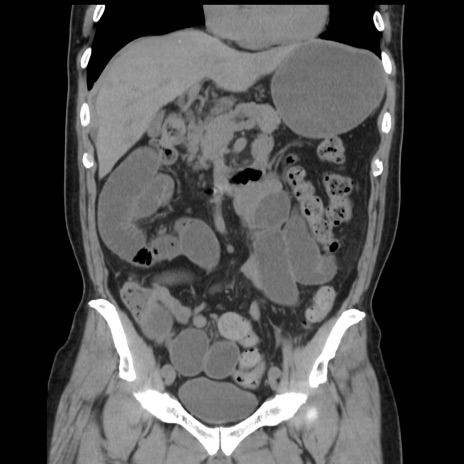

症例16(冠状断像)

【症例】 70歳代男性

【主訴】 腹痛、嘔吐

【現病歴】 約1ヶ月前より間欠的に腹痛と嘔吐あり、当院消化器内科を受診したところCTで多発する肝臓のLDAを指摘され、精査中であった。以降は消化器症状は安定していたが、2日前より嘔気と腹痛があり、同日より排便・排ガスが消失した。改善認めず、 本日、救急外来を受診した。

【既往歴】 大腸ポリープ切除後。

【身体所見】意識清明・会話良好、BT 36.3℃、BP 127/80mmHg、 P 80bpm、腹部:膨満あり、平坦・軟、上腹部正中および下腹部正中に圧痛あり、反跳痛なし、筋性防御なし。

【データ】WBC 7200、CRP 0.77